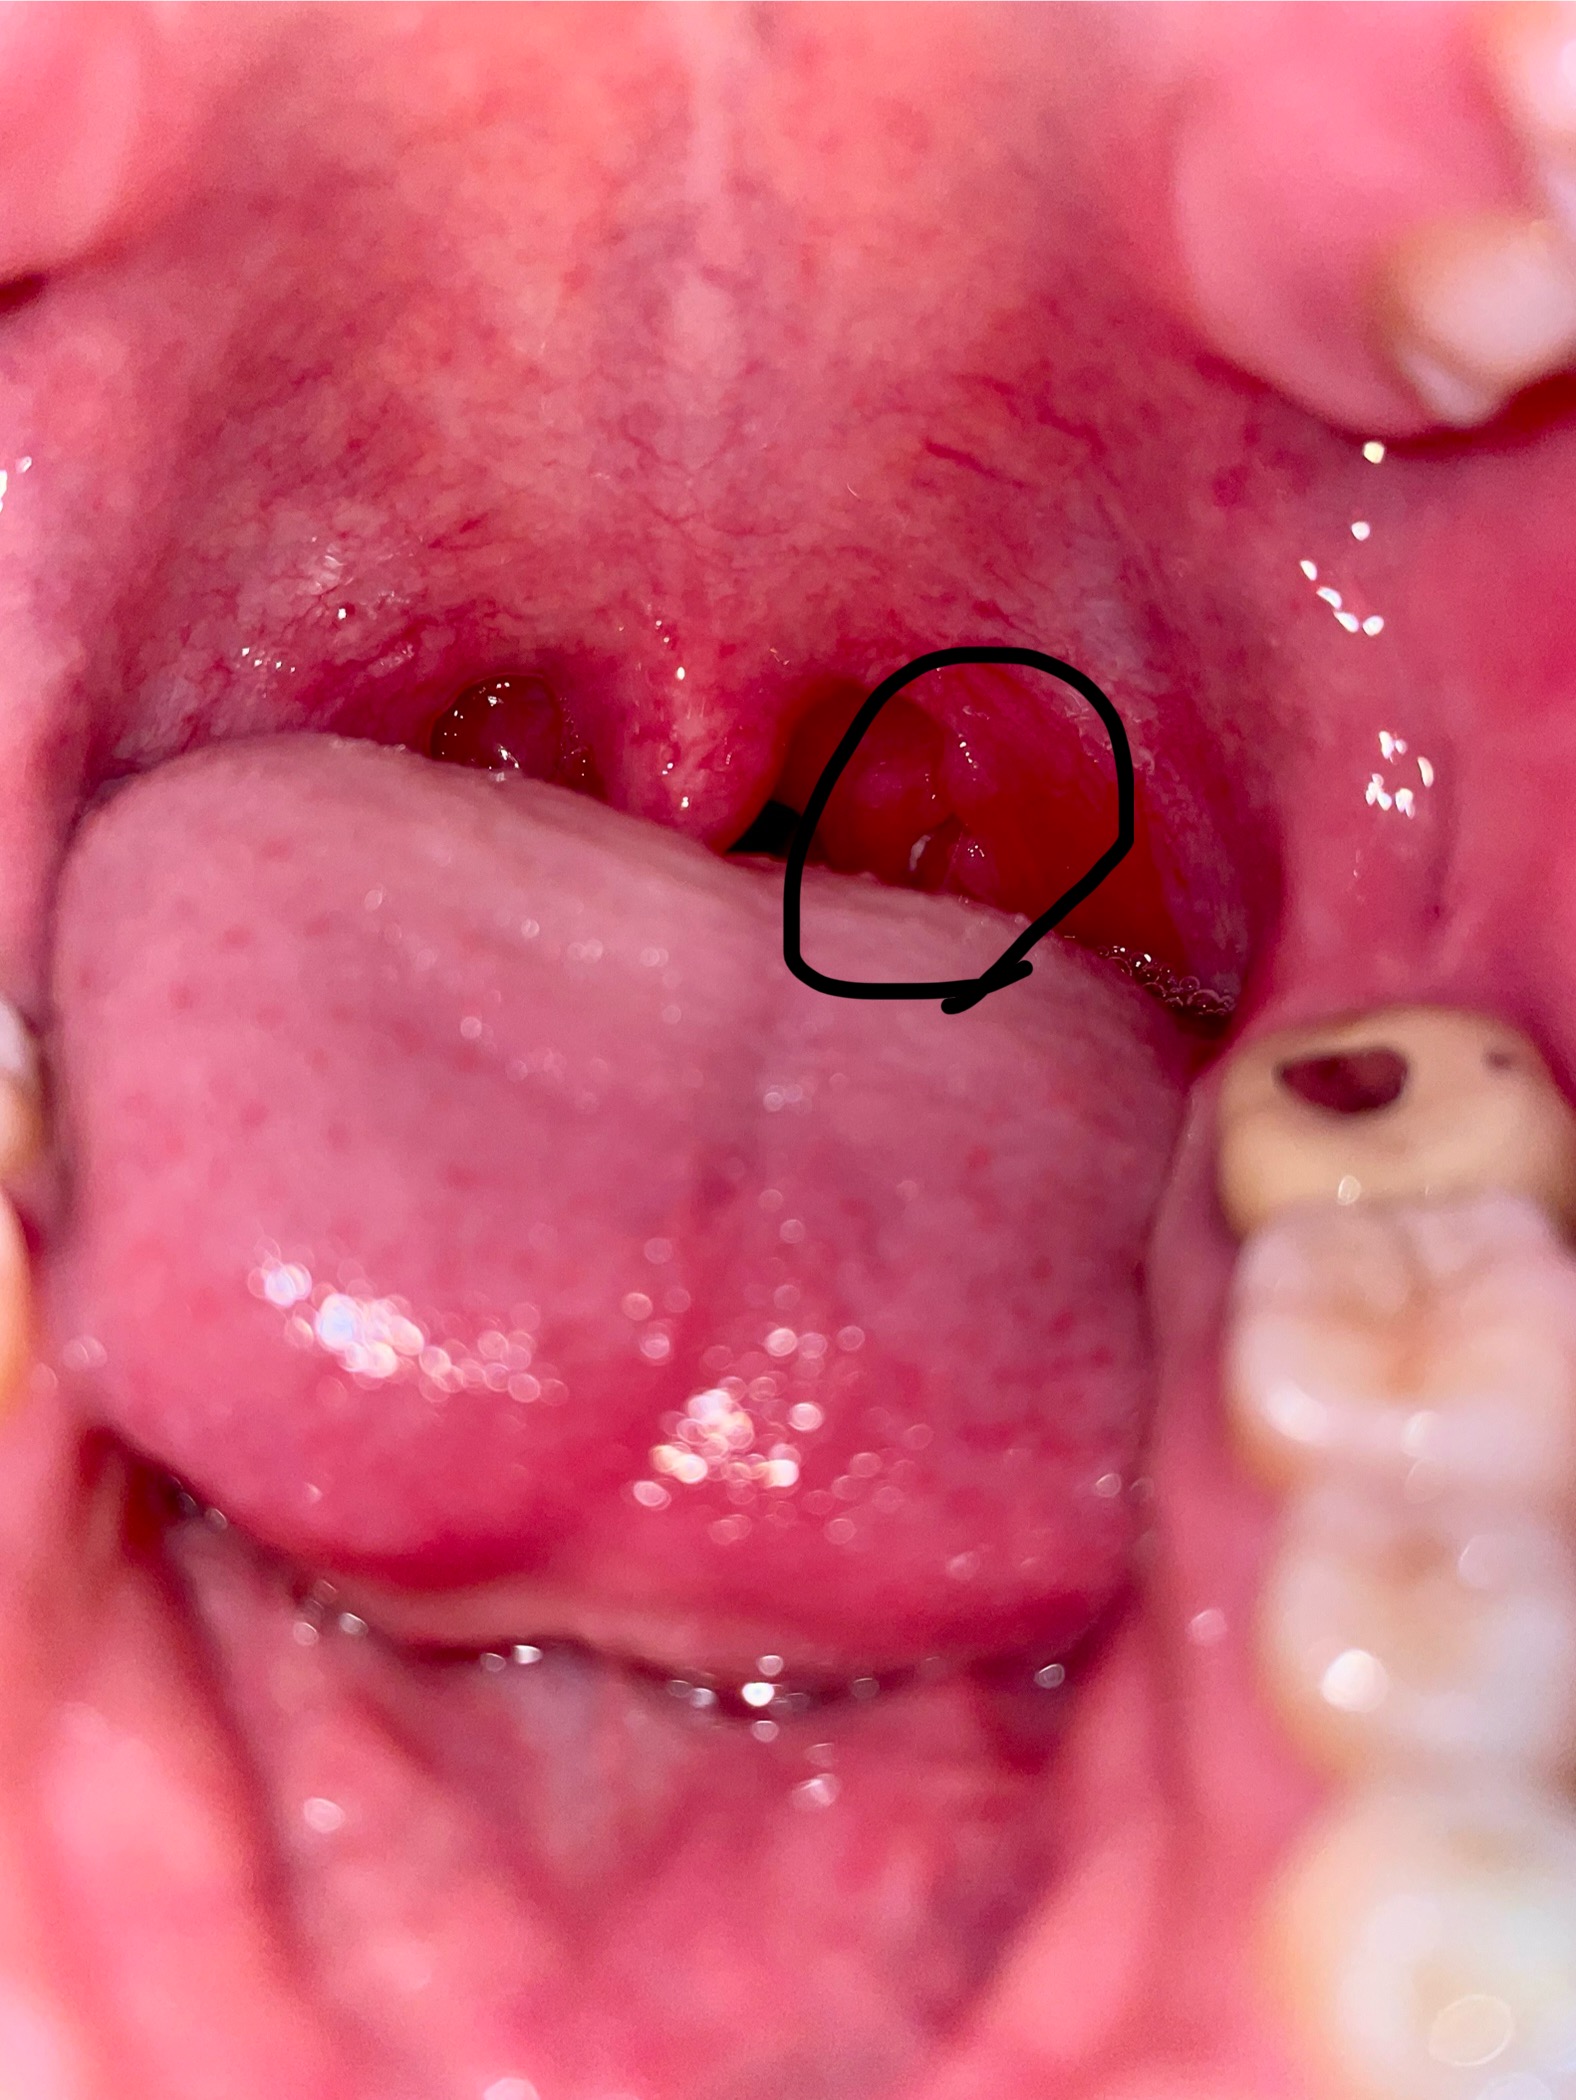

28 กรกฎาคม 2568 20:12:11 #1 มีติ่งเนื้อ 2-3 ติ่ง ที่ต่อมทอลซิลข้างซ้าย อีกข้างปกติ https://haamor.com/media/create_topic/20250728200842.jpeg https://haamor.com/media/create_topic/202507282008421.jpeg อยากทราบว่าเป็นติ่งเนื้ออะไร ผิดปกติไหมครับ |

30 กรกฎาคม 2568 13:02:05 #2 เป็นเนื้อของต่อมทอลซิลที่อักเสบจากการติดเชื้อครับ ควรไปพบแพทย์ครับ |